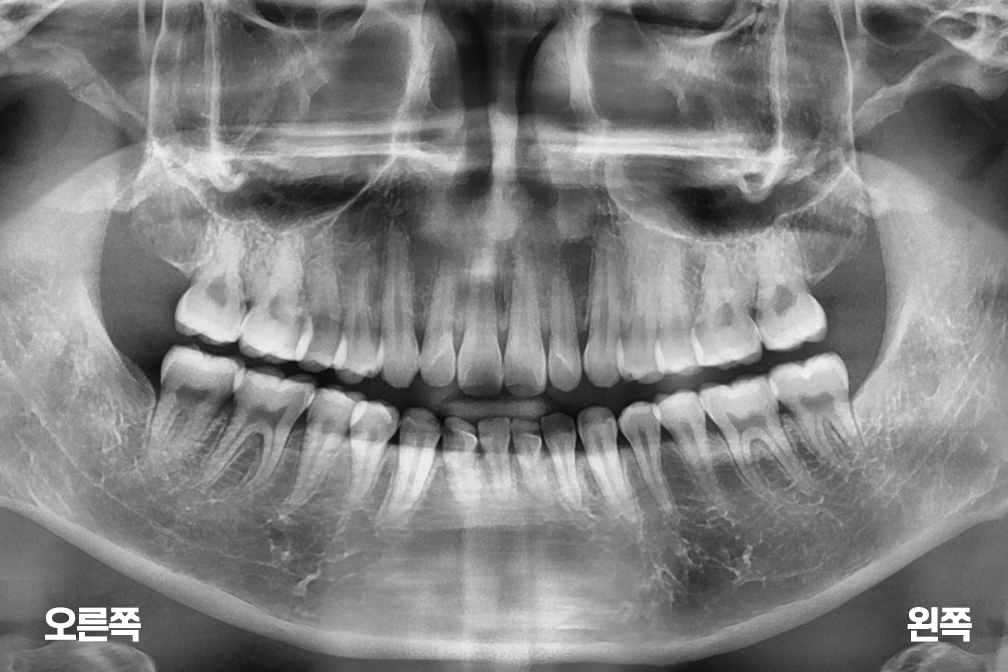

사랑니발치 4개의 사랑니 발치

사랑니 발치

위 전후사진은 이미지사진으로 실제 눈으로 보는 것과는 다를 수 있으며, 환자의 치아상태과 방법에 따라 치료결과가 다를수 있습니다.

사진의 날짜는 촬영날짜이며 치료의 기간이 아님을 알려드립니다.

치료 후 치아표면의 탈회 , 충치, 치근흡수 등의 부작용이 있을 수 있습니다.